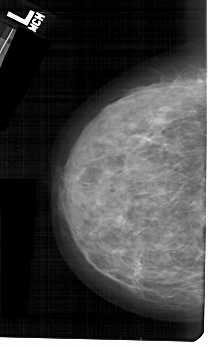

A_1367_1.LEFT_MLO

LEFT_MLO LINES 5491 PIXELS_PER_LINE 3331 BITS_PER_PIXEL 12 RESOLUTION 43.5 NON_OVERLAY